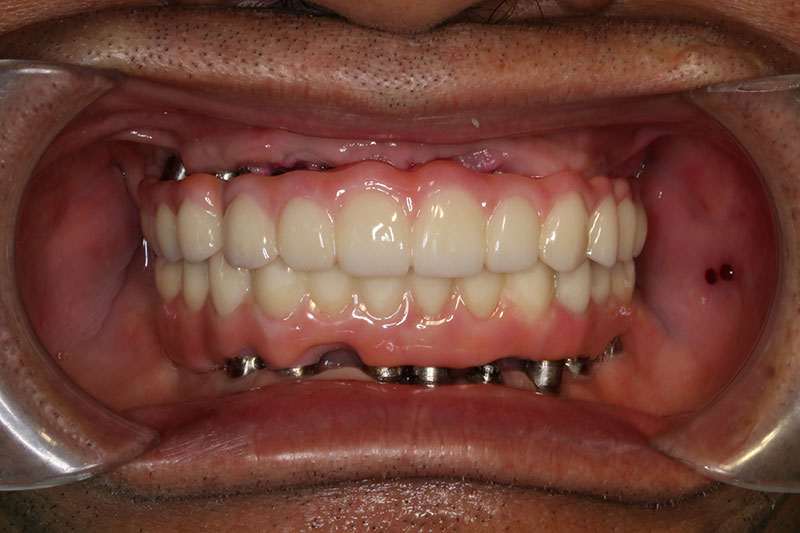

銀髮族植牙 全口植牙重建

案例一

術前

術後